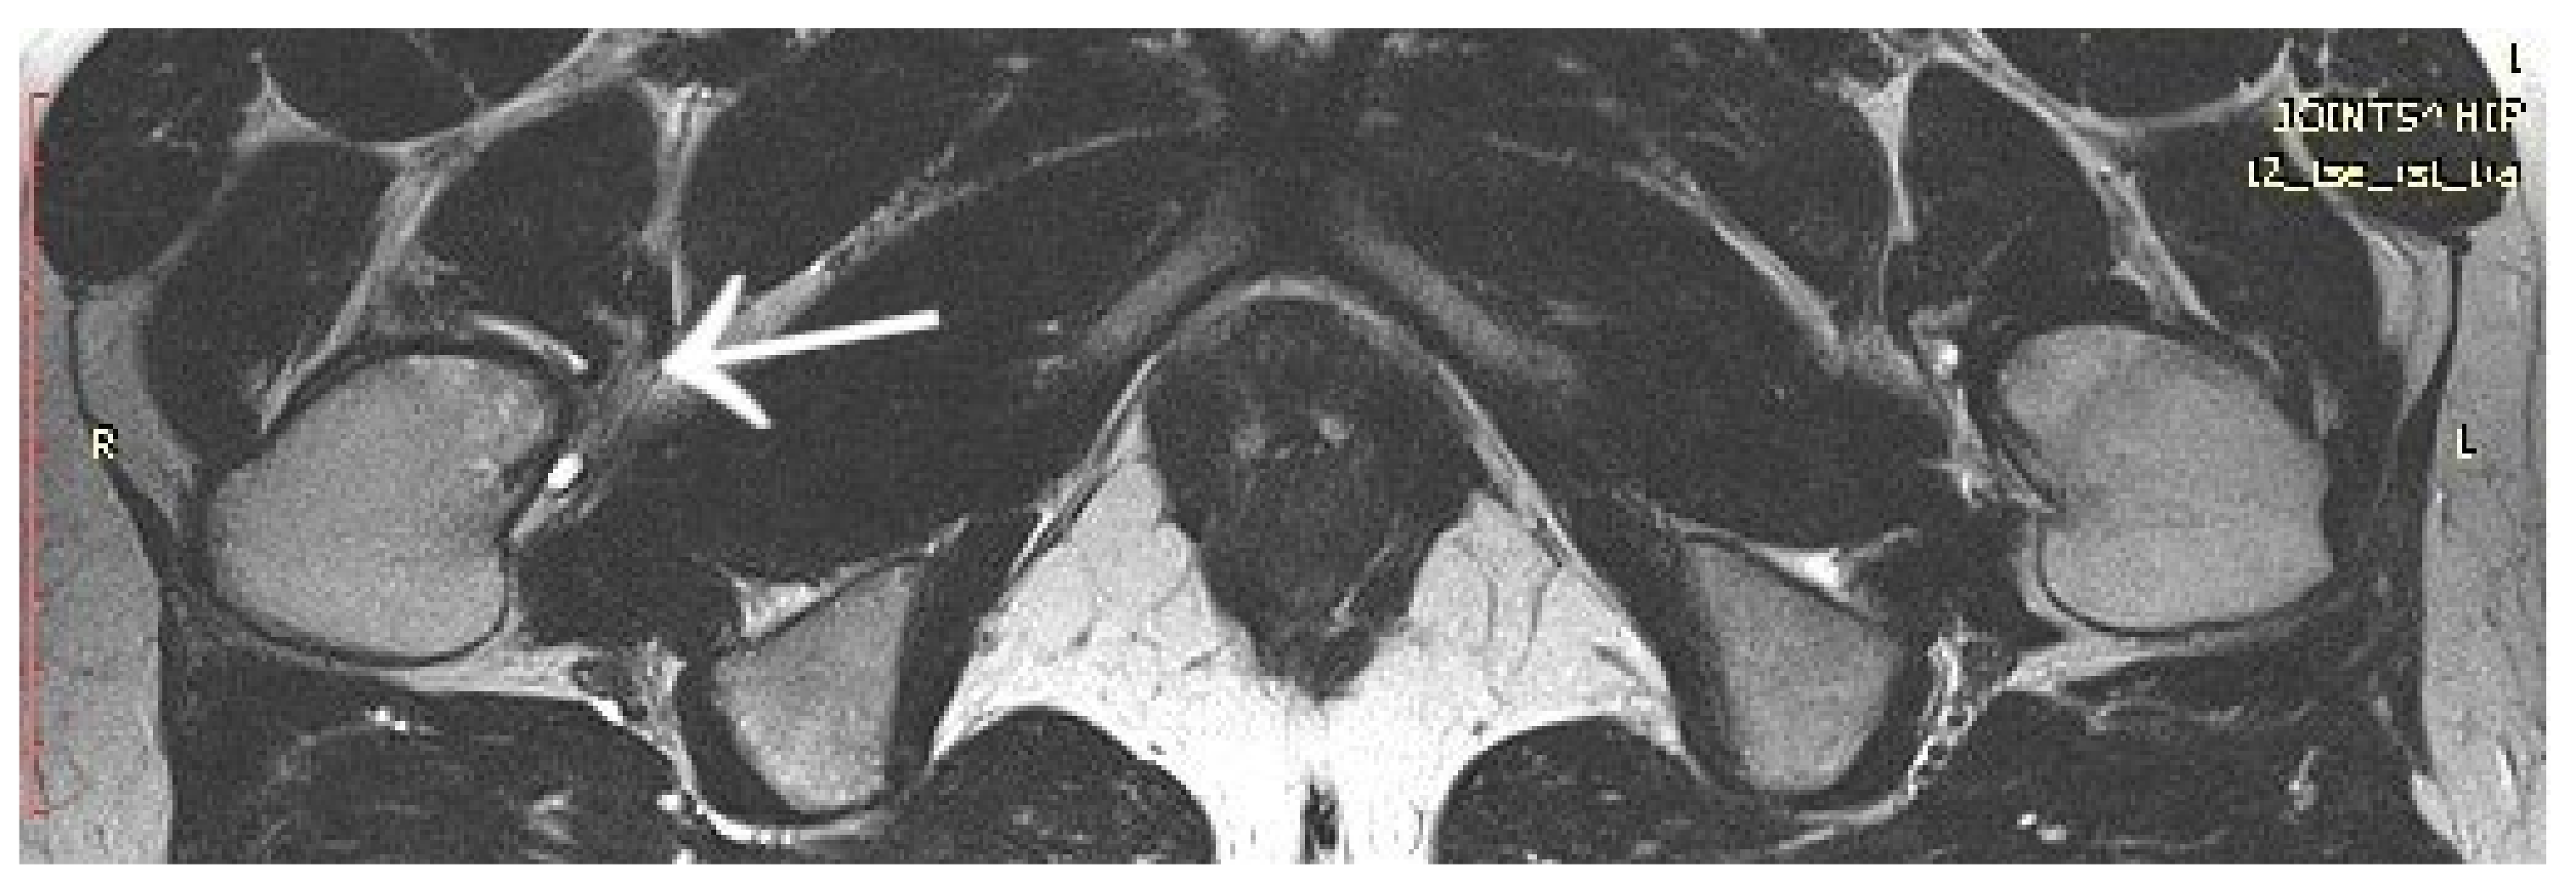

Figure 12.

First MRI scan of the hip joints with visible focus of OO (arrow) in the femoral head/neck border, unnoticed.

A 14-year-old female patient presented with a history of two years of pain in the left hip with a limp in her leg. The pain occurred mainly at night, waking her from her sleep. The girl associated the onset of her symptoms with an injury. The patient gave a history of a prolonged diagnostic process: 12 hospitalisations, four MRI scans, and numerous X-ray and ultrasound examinations. In the results provided, the first MRI scan already showed a small lesion in the left femoral neck, which was not described in the interpretation of the MRI scans (Figure 12). Based on the MRI scan with the description of bone marrow oedema and the features of synovitis, the patient was admitted to the Paediatrics Department with suspected hip arthritis, treated with antibiotic therapy. Six months later, during another hospitalisation for suspected hip arthritis, laboratory tests showed HLA-B27 antigen, weakly positive antinuclear antibodies, and a positive tuberculin test. The patient was urgently hospitalised at the Lung and Tuberculosis Centre with a diagnosis of latent tuberculosis. With suspected tuberculous hip arthritis, a cortical and synovial biopsy was performed. Treatment with isoniazid for 9 months was administered. Synovitis was present in the biopsy specimen. During a subsequent hospitalisation in the Developmental Age Rheumatology Department, juvenile idiopathic arthritis was diagnosed, and HLA-B27 antigen was detected. The patient was started on methotrexate. At subsequent hospitalisations, treatment with chloroquine and sulfasalazine was started, maintaining treatment with methotrexate. With no signs of improvement, the patient was qualified for biological therapy. In the meantime, a suspicion of femoroacetabular impingement was raised during a series of additional examinations. After almost two years of incorrect diagnosis and treatment, a CT scan of the left hip joint was performed for the first time. The image revealed an osteolytic lesion of 7 × 7 × 6 mm (Figure 13). The description showed the features typical of OO. The patient was qualified for thermoablation with intraoperative 3D navigation. On the day of surgery, the patient presented the limitation of mobility of the left hip joint with VAS 8 hip pain. The day after surgery, the VAS score was 3. On examination 2 months after surgery, there was complete resolution of pain with full mobility of the left hip joint.